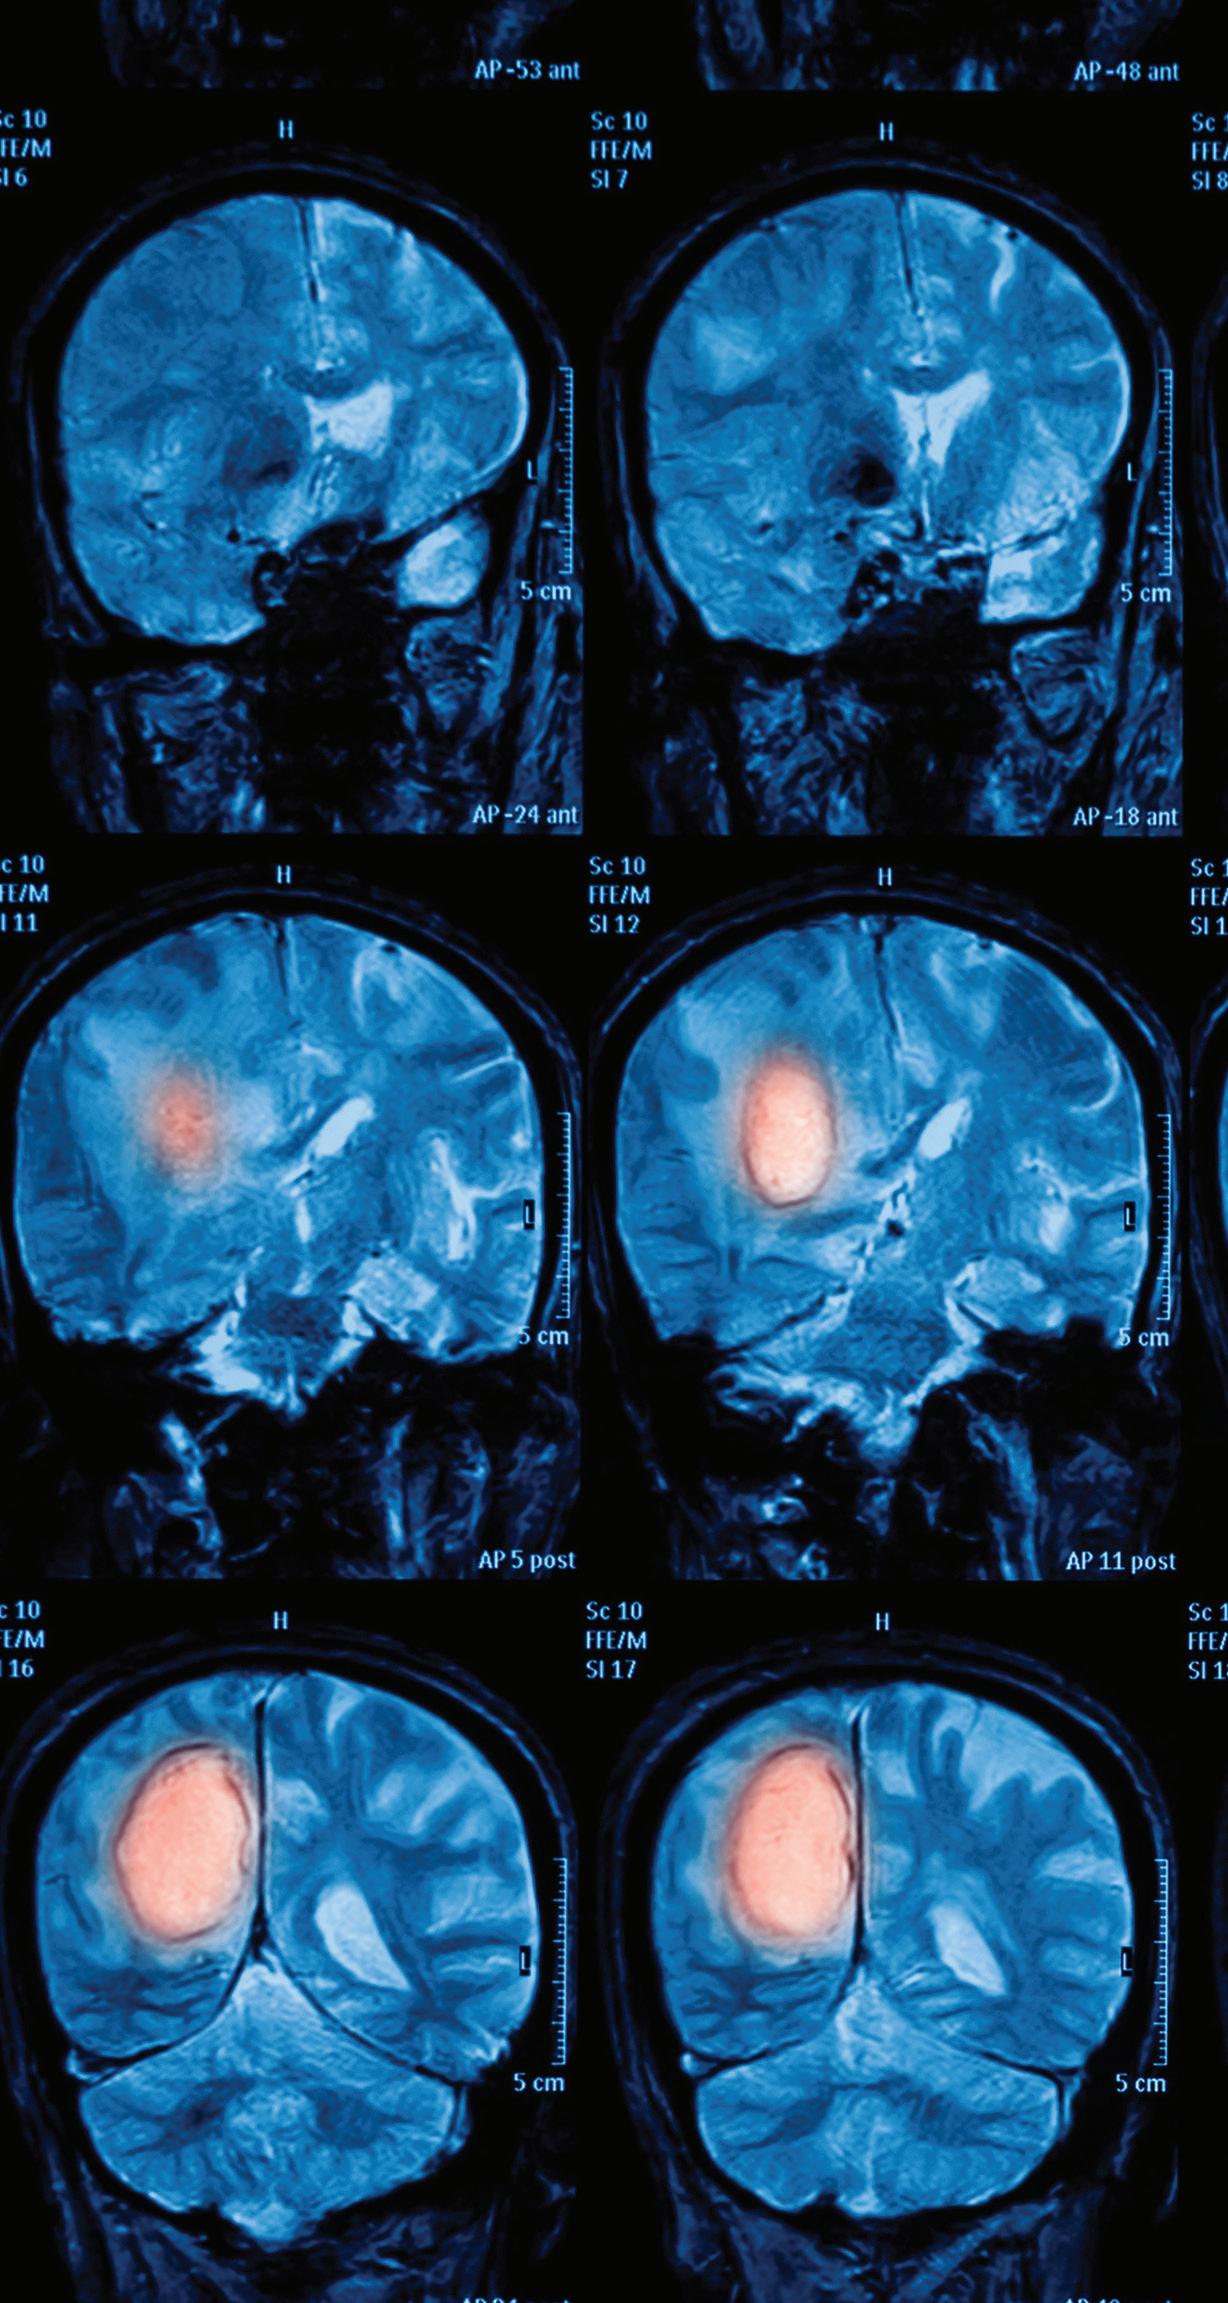

Advancing the Treatment of Brain Tumors

Through her studies at Johns Hopkins, Yale New Haven Hospital, and Memorial Sloan Kettering Cancer Center, Toral Patel, M.D., learned from some of the top engineers and surgeons in the world. Now, as Director of the UT Southwestern Brain Tumor Program, she’s integrating her background in biomedical engineering with a patient-centric approach to clinical care.

Magnetic resonance imaging (MRI) of the brain, brain tumor.